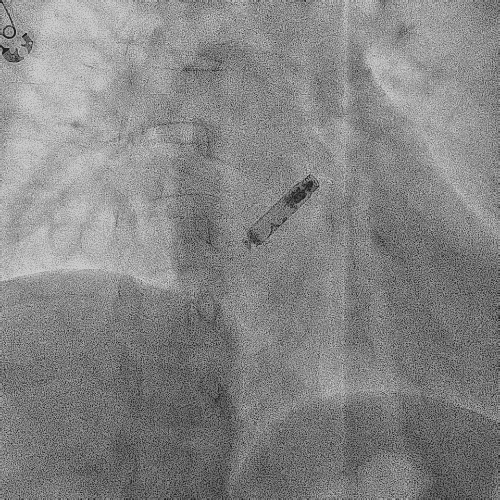

在心房和心室电极成功拔除后,患者立刻感觉“眼前一亮”,颜面肿胀感缓解,此时颈静脉怒张相比术前也明显缓解。再次复查上腔静脉造影,狭窄明显减轻,无需再使用上腔静脉扩张球囊进行扩张。

电极拔除后

颈静脉怒张

明显缓解

上腔静脉狭窄